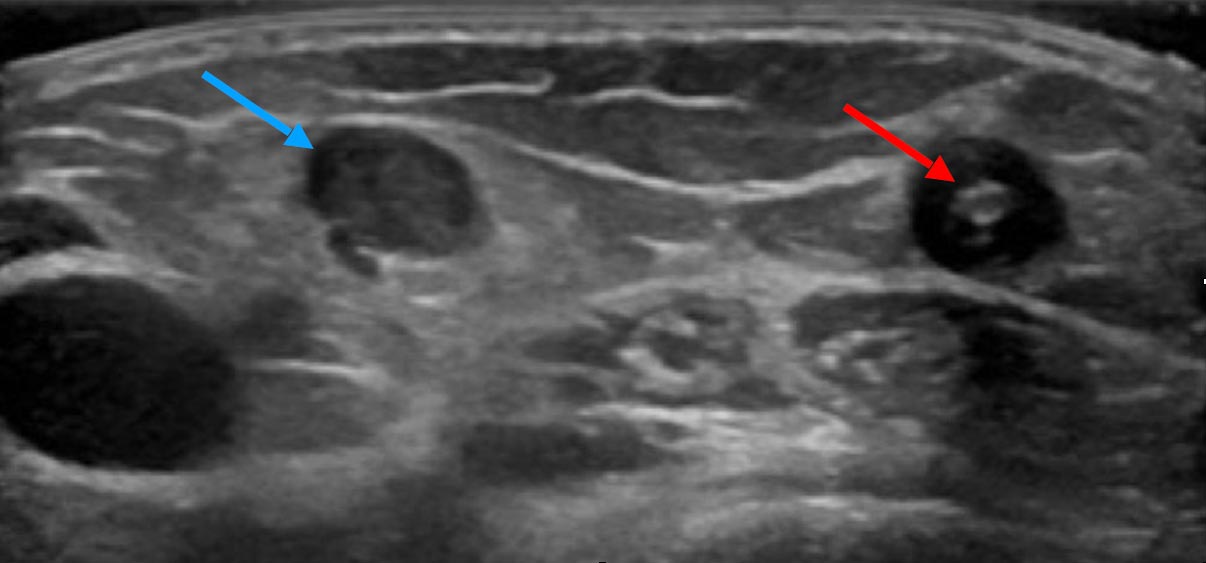

If imaging is ever necessary, sonography is the first choice. Thrombophlebitis is easily visualized within the anechoic venous malformation components as echogenic, non-compressible circumscribed foci.

On sonography, a normal vein or venous malformation is soft and readily compressible with the transducer. The non-clotted blood is virtually anechoic (black), and slow blood flow is detectable on color-coded duplex sonography.

As the blood clot matures with time, it becomes more echogenic sonographically, making it easy to distinguish from anechoic blood. Often starting at the edge, i.e., at the vessel wall, there is a slow recanalization of the involved vessel. This is visible as anechoic fluid around the echogenic thrombus.

An important indicator of recurrent thrombophlebitis in the past may be the number of phleboliths present within the venous malformation (e.g., seen in ultrasound or X-ray). As a rule of thumb, the more frequently thrombophlebitis occurred in the past, the more frequently phleboliths are detectable. Patients with multiple phleboliths are more often symptomatic and also benefit from invasive therapy.